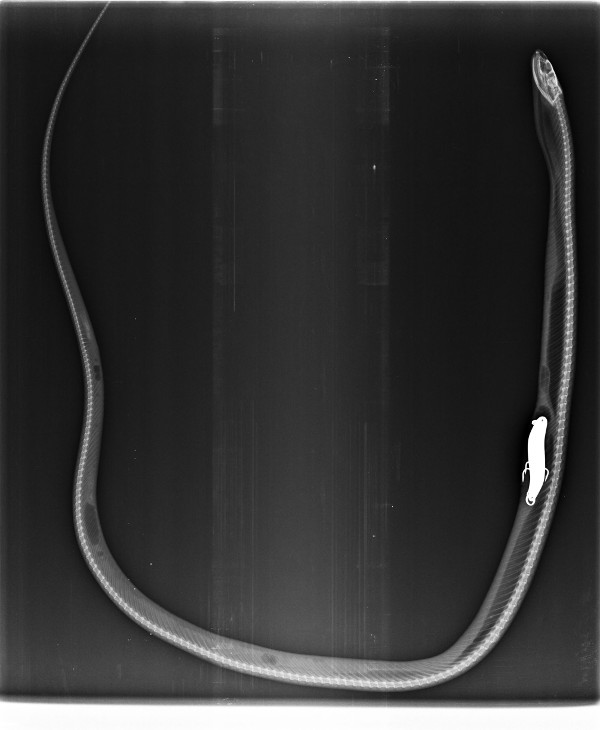

Radiografía frontal de la culebra de collar, con el señuelo de pesca en su interior.

Radiografía lateral de la culebra de collar, con el señuelo de pesca en su interior.

Nada más llegar el animal al Hospital de Fauna Salvaje de GREFA se le realizaron varias radiografías que mostraron que dicho anzuelo pertenecía a un señuelo de pesca que el animal había ingerido suponemos que confundiéndolo con alimento, ya que se trata de un reptil de costumbres acuáticas. Tras ser estabilizada, la culebra de collar fue sometida a una cirugía en la que se le extrajo mediante enterotomía (apertura de la pared intestinal) el señuelo cuidando mucho no dañar más el sistema digestivo del animal.